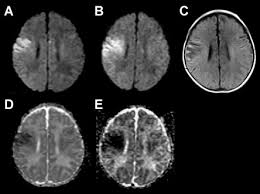

Lesions similar to cytotoxic edema, and lesions similar to vasogenic edema. Seizure, altered sensorium, fever frontal and temporal lobes, rarely extratemporal t2 hyperintensity, restricted diffusion, sometimes. Herpes encephalitis is the most common sporadic encephalitis in the united states and other industrialized countries .occurring as either a primary infection with herpes simplex virus or as a reactivation of latent virus, herpes encephalitis causes significant morbidity and mortality .early intervention with acyclovir significantly improves outcome; The clinical syndrome is often characterized by the rapid onset of fever, headache, seizures, focal neurologic signs, and impaired consciousness 1 . Having said that, mri with contrast is considered the most sensitive imaging modality, and findings are present in over half of individuals 8. The patients with the former type of lesions had fulminating disease, and were in severe clinical condition. Herpes simplex encephalitis occurs as 2 distinct entities: 4 it was found that, rather surprisingly, varicella zoster virus (vzv), the cause of chickenpox and herpes zoster, was the most frequently detected virus at 29%, with hsv and enteroviruses accounting for 11% of cases. Two subtypes are recognized which differ in demographics, virus, and pattern of involvement. (1)department of radiology, ankara numune education and research hospital, ankara, turkey. Neonatal herpes simplex encephalitis is caused by vertical transmission of infection during passage from birth canal with diffuse cerebral involvement within the first month after birth; As the older term limbic encephalitis implies, the most common location of involvement is the mesial temporal lobes and limbic systems, typically manifested by cortical thickening and increased t2/flair. In patients with herpes encephalitis, two distinct types of diffusion imaging findings (on b =1000 s/mm 2 images, and adc maps) were noted:

We present mri findings of two cases of herpes simplex encephalitis (hse) confirmed by pcr analysis, focusing on the serial changes after acyclovir therapy: 4 it was found that, rather surprisingly, varicella zoster virus (vzv), the cause of chickenpox and herpes zoster, was the most frequently detected virus at 29%, with hsv and enteroviruses accounting for 11% of cases. mri findings of herpes simplex encephalitis. For viral infection of the meninges, please refer to the general article on viral meningitis, and, for a broad view on the curriculum of infections of the central nervous system, refer to cns. The patients with the former type of lesions had fulminating disease, and were in severe clinical condition. The kappa value for interobserver agreement on rating the scans as normal or abnormal was good (0.65) for ct and moderate (0.59) for mri. Noguchi t, yoshiura t, hiwatashi a, et al. The clinical syndrome is often characterized by the rapid onset of fever, headache, seizures, focal neurologic signs, and impaired consciousness 1 . The patients with the former type of lesions had fulminating disease, and were in severe clinical condition. Specific diagnosis often requires pcr. As the older term limbic encephalitis implies, the most common location of involvement is the mesial temporal lobes and limbic systems, typically manifested by cortical thickening and increased t2/flair. In patients with herpes encephalitis, two distinct types of diffusion imaging findings (on b =1000 s/mm 2 images, and adc maps) were noted: A recent study in finland also used pcr to detect various viruses in the csf of over 3000 patients who had infections of the cns including encephalitis, meningitis, and myelitis.

Specific diagnosis often requires pcr. Normal mr imaging findings (type 1, 53% of patients), isolated hippocampal involvement (type 2, 13%), other brain lesions without hippocampal involvement (type 3, 13%), and other brain lesions with hippocampal involvement (type 4, 21%). In patients with herpes encephalitis, two distinct types of diffusion imaging findings (on b =1000 s/mm 2 images, and adc maps) were noted: Watershed distribution ischemia in areas remote from the primary herpetic lesions may be seen. article in japanese yoshioka a, hirose g, tsukada k, oda r, kosoegawa h.

The patients with the former type of lesions had fulminating disease, and were in severe clinical condition. The diagnosis of hse is based on laboratory investigations, magnetic resonance (mr) imaging findings, electroencephalogram and, occasionally, a biopsy. Herpes encephalitis is the most common sporadic encephalitis in the united states and other industrialized countries .occurring as either a primary infection with herpes simplex virus or as a reactivation of latent virus, herpes encephalitis causes significant morbidity and mortality .early intervention with acyclovir significantly improves outcome; Herpes simplex (hsv) encephalitis is the most common cause of fatal sporadic fulminant necrotising viral encephalitis and has characteristic imaging findings. In patients with herpes encephalitis, two distinct types of diffusion imaging findings (on b =1000 s/mm 2 images, and adc maps) were noted: Relapse of encephalitis occurs in up to 10% of patients, manifested by recurrent symptoms, clinical and mri findings, and the presence of herpes simplex virus type 1 dna in the cerebrospinal fluid (csf). In children older than 3 months and in adults, hse is usually localized to the temporal and frontal lobes and is c. In patients with herpes encephalitis, two distinct types of diffusion imaging findings (on b =1000 s/mm 2 images, and adc maps) were noted: Herpes simplex (hsv) encephalitis is the most common cause of fatal sporadic fulminant necrotizing viral encephalitis and has characteristic imaging findings. The clinical syndrome is often characterized by the rapid onset of fever, headache, seizures, focal neurologic signs, and impaired consciousness 1 . We present mri findings of two cases of herpes simplex encephalitis (hse) confirmed by pcr analysis, focusing on the serial changes after acyclovir therapy: Two subtypes are recognised which differ in demographics, virus, and pattern of involvement. Despite advances in antiviral therapy over the past 2 decades, herpes simplex encephalitis (hse) remains a serious illness with significant risks of morbidity and death.